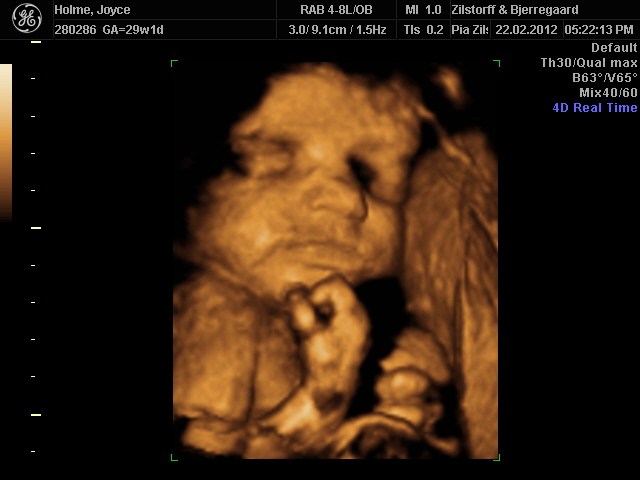

Her er lige et par billeder af vores lille babypige